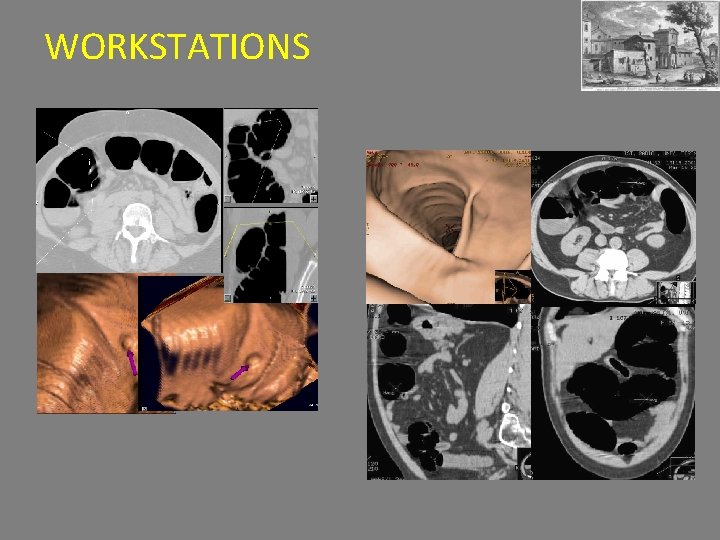

COLONSCOPIA VIRTUALE REFERTAZIONE - Ricostruzione delle immagini su diversi piani - Navigazione su workstation dedicate (CAD COLON) - Identificazione lesioni pre-cancerose(polipi >6 mm ) e cancerose - Valutazione organi addominali nelle sole condizioni basali

WORKSTATIONS